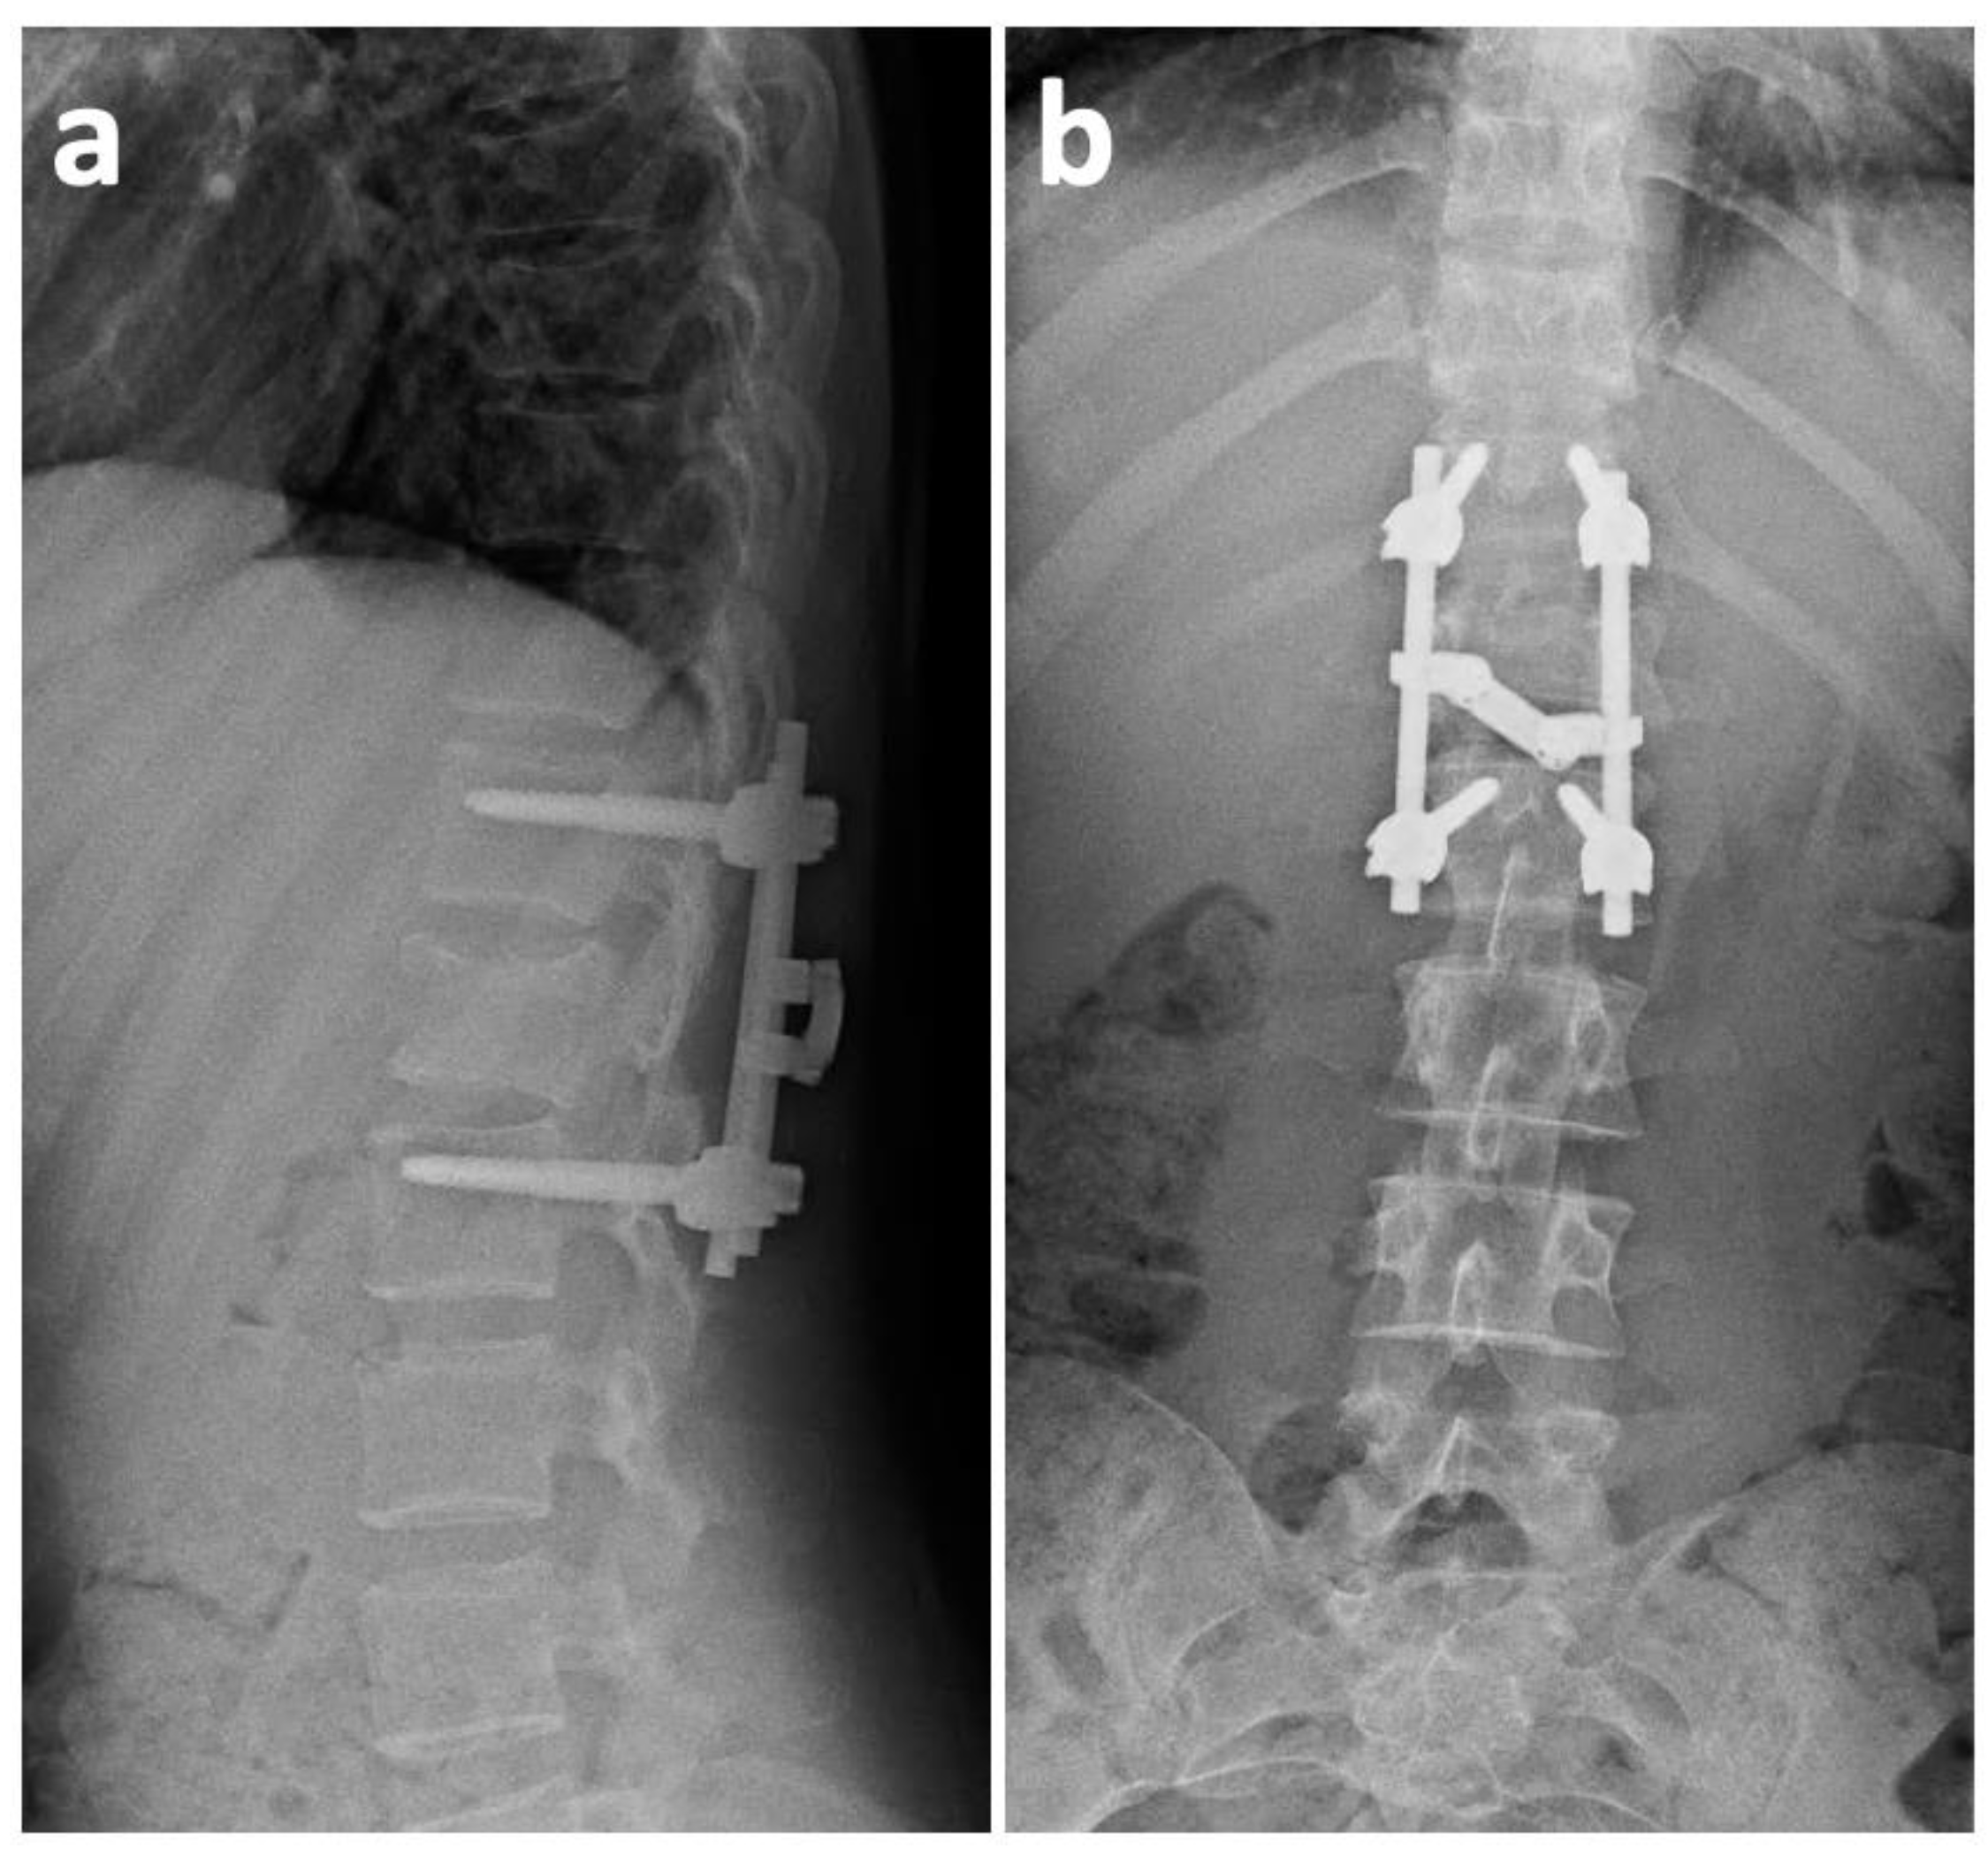

2. Case History